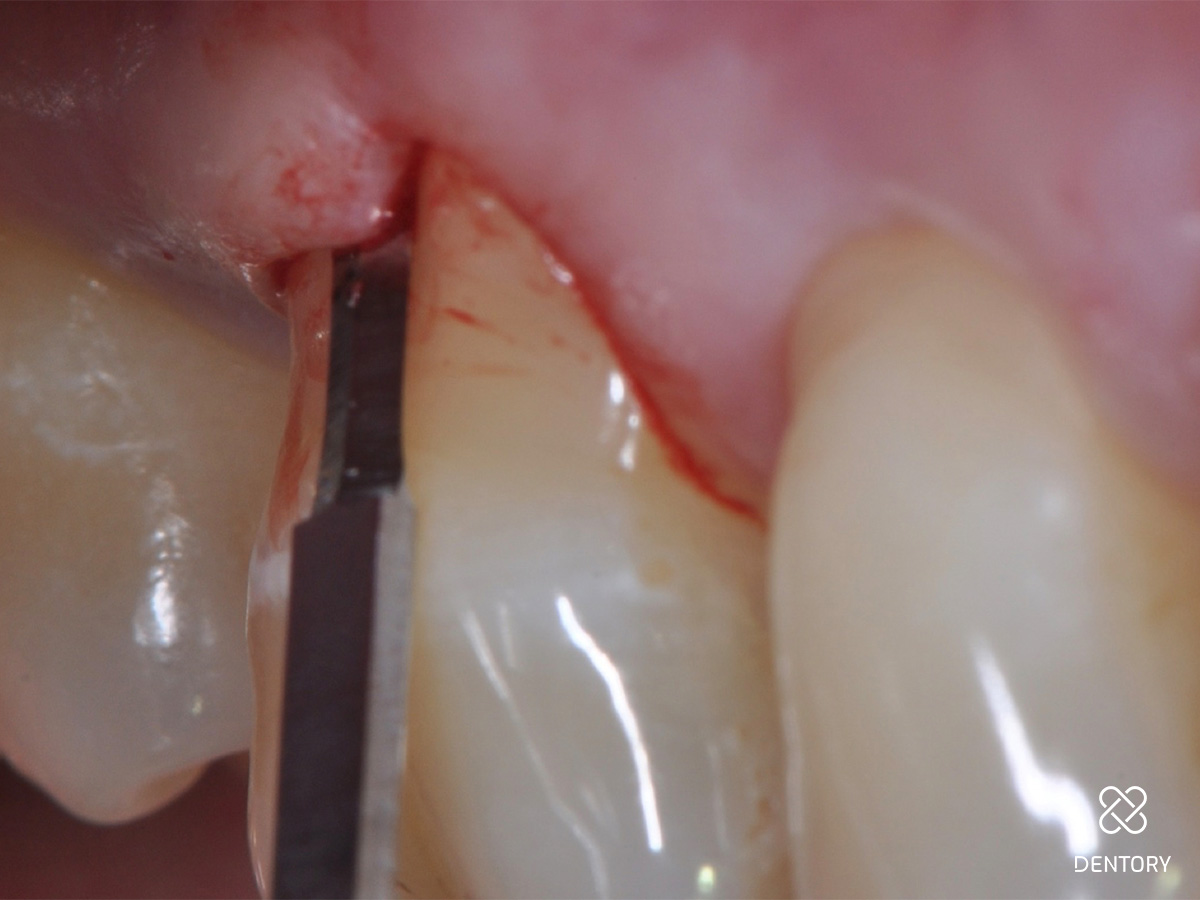

Abbildung 2

Die Ausgangssituation der regio 16/17. Hier wurden initial Sondierungstiefen von 9 und 11 mm mesial an Zahn 17 gemessen.